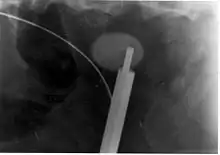

Where a CT scan is unavailable, an intravenous pyelogram may be performed to help confirm the diagnosis of urolithiasis. This involves intravenous injection of a contrast agent followed by a KUB film. Uroliths present in the kidneys, ureters, or bladder may be better defined by the use of this contrast agent. Stones can also be detected by a retrograde pyelogram, where a similar contrast agent is injected directly into the distal ostium of the ureter (where the ureter terminates as it enters the bladder).[56]

Bilateral kidney stones can be seen on this KUB radiograph. There are phleboliths in the pelvis, which can be misinterpreted as bladder stones.

Renal ultrasonograph of a stone located at the pyeloureteric junction with accompanying hydronephrosis.